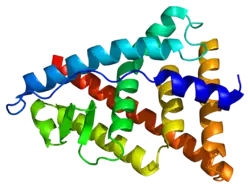

Estrogen receptor beta (ERβ) also known as NR3A2 (nuclear receptor subfamily 3, group A, member 2) is one of two main types of estrogen receptor—a nuclear receptor which is activated by the sex hormone estrogen.[5] In humans ERβ is encoded by the ESR2 gene.[6]

ERβ is a member of the family of estrogen receptors and the superfamily of nuclear receptor transcription factors. The gene product contains an N-terminal DNA binding domain and C-terminal ligand binding domain and is localized to the nucleus, cytoplasm, and mitochondria. Upon binding to 17-β-estradiol, estriol or related ligands, the encoded protein forms homo-dimers or hetero-dimers with estrogen receptor α that interact with specific DNA sequences to activate transcription. Some isoforms dominantly inhibit the activity of other estrogen receptor family members. Several alternatively spliced transcript variants of this gene have been described, but the full-length nature of some of these variants has not been fully characterized.[7]